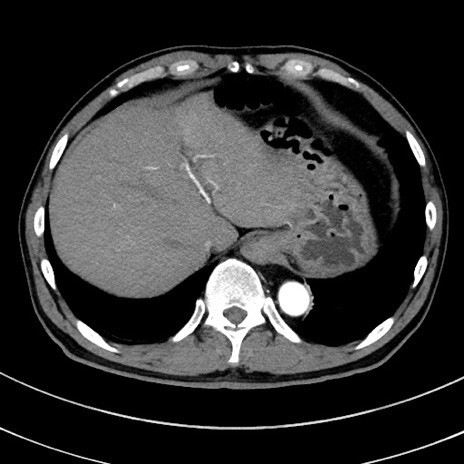

症例8(横断像)

【症例】 60歳代男性

【主訴】 黒色吐物

【現病歴】 4日前から嘔気自覚、2日前の朝食後にも嘔気あり、自分で手で嘔吐反射起こし嘔吐したところ血が混ざっていたため受診。

【既往歴】 5年前汎発性腹膜炎を伴う急性虫垂炎で手術、高血圧、前立腺肥大症、高脂血症

【身体所見】 腹部正中に手術癩痕あり 腹部平坦・軟圧痛なし膨満感あり

【データ】WBC 8400、CRP 4.54